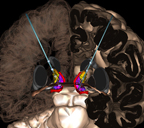

Terminals and pathways effected during deep brain stimulation (DBS) DBSreview- Overview of deep brain stimulation. : 3.1 DBS at the internal capsule site, what it gets and what it doesn’t get DBS Model of electrode in internal capsule.